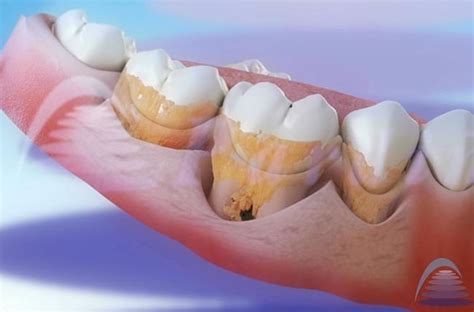

El sarro que se acumula bajo la línea de la encía -conocido como sarro subgingival- es especialmente perjudicial, ya que no es visible a simple vista y puede avanzar de forma silenciosa, comprometiendo el hueso y los tejidos que sostienen el diente.

En muchos casos, el sarro supragingival es visible: se presenta como una línea amarillenta o marrón entre los dientes y la encía. Por el contrario, el sarro subgingival requiere una evaluación profesional.

Imagen de Wikimedia Commons, autor: Dozenist

En una clínica dental, se detecta mediante una exploración con sonda periodontal y, si es necesario, con radiografías para evaluar el estado del hueso.

El Sarro Duro Detrás de los Dientes

El sarro duro detrás de los dientes afecta a más del 70% de los adultos (según la Encuesta de Salud Oral en España 2020), convirtiéndose en una de las principales causas de enfermedades periodontales. Este problema requiere un enfoque profesional y especializado para su correcta eliminación.

La anatomía oral explica por qué el sarro duro detrás de los dientes inferiores es tan común. Las glándulas sublinguales y submandibulares, ubicadas debajo de la lengua, secretan constantemente saliva rica en minerales directamente hacia la superficie lingual de los incisivos inferiores.